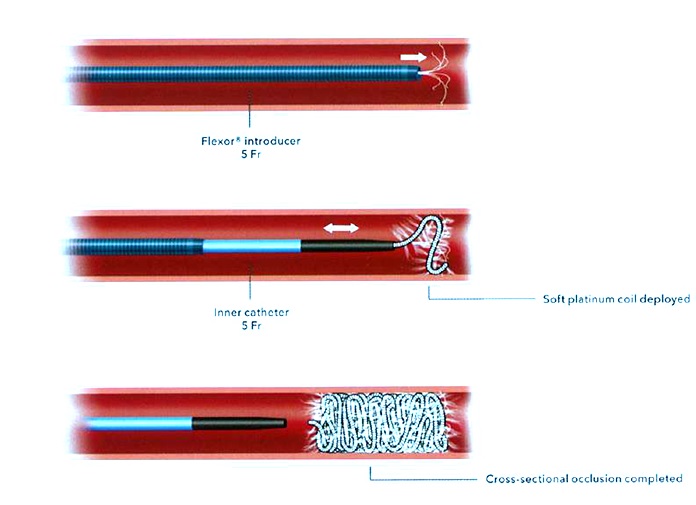

技术之二,锚定和脚手架技术:主要用于大动脉阻塞,将弹簧栓子部分锚定在血管的某一分支上。弹簧栓子的直径>血管直径。往复推送弹簧栓子(go to and fro and push)

脚手架技术(Scaffold technique)

|

|

选用较大的弹簧栓子,利用高径向支撑力。可推式弹簧栓子的脚手架(Scaffold)技术。先非致密性阻塞血管,再将推送管重新推回起始点在释放弹簧栓子。 |